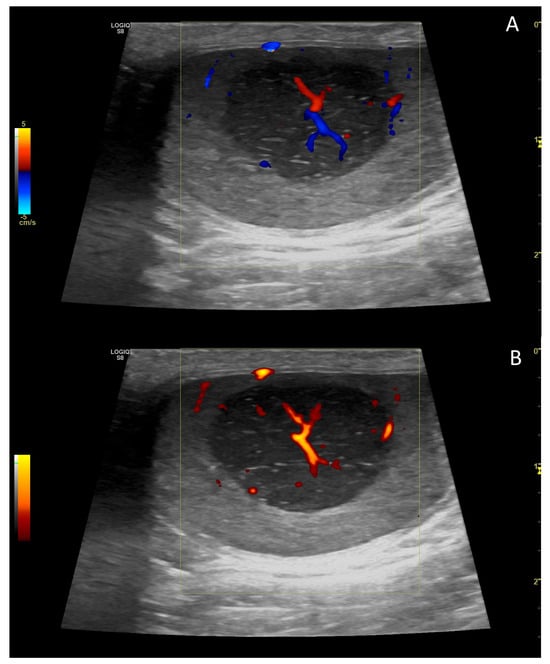

4. Colour Doppler and Power Doppler

4.1. Technology and Applications

4.2. Normal Findings

4.4. Abnormal Findings